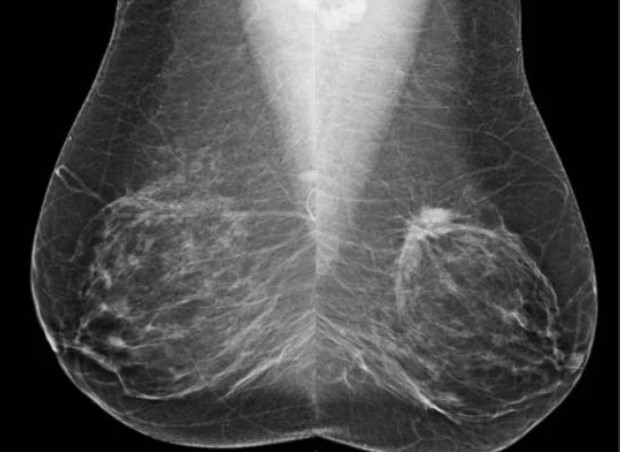

유방촬영에 의해서 임상적인 발견에 앞서 초기 유방암에 연관된 세부적인 변화를 관찰할 수 있습니다.

유방암의 조기진단은 주로 유방자가검진, 유방촬영술과 초음파 검사 등을 통하여 이루어집니다. 이 중 유방촬영술은 증상이 있기 이전에 종양을 발견할 수 있는 장점이 있습니다.

유방촬영술은 1cm 미만 종괴의 발견이 가능하며 유방암의 아주 초기 단계인 비침습성암 (관상피내암)의 발견율이 높습니다.